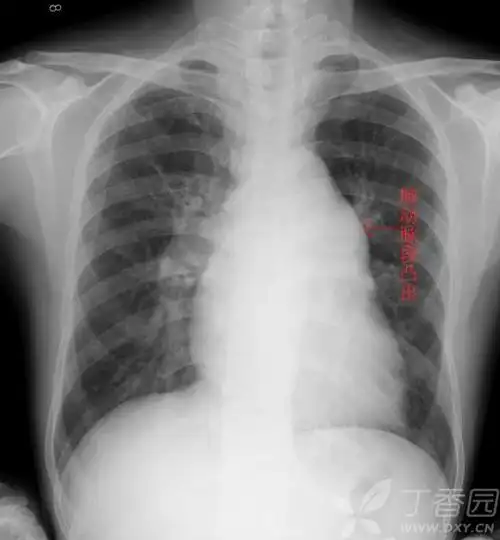

普大型心梨形心靴形心的片子究竟怎么看啊丁香园